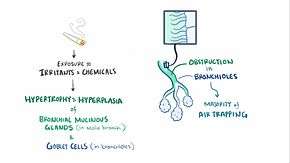

COPD is a type of obstructive lung disease in which chronic incompletely reversible poor airflow (airflow limitation) and inability to breathe out fully (air trapping) exist.[5] The poor airflow is the result of breakdown of lung tissue (known as emphysema) and small airways disease (known as obstructive bronchiolitis). The relative contributions of these two factors vary between people.[1] Severe destruction of small airways can lead to the formation of large air pockets—known as bullae—that replace lung tissue. This form of disease is called bullous emphysema.[52]

COPD develops as a significant and chronic inflammatory response to inhaled irritants.[1] Chronic bacterial infections may also add to this inflammatory state.[50] The inflammatory cells involved include neutrophil granulocytes and macrophages, two types of white blood cell. Those who smoke additionally have Tc1 lymphocyte involvement and some people with COPD have eosinophil involvement similar to that in asthma. Part of this cell response is brought on by inflammatory mediators such as chemotactic factors. Other processes involved with lung damage include oxidative stress produced by high concentrations of free radicals in tobacco smoke and released by inflammatory cells, and breakdown of the connective tissue of the lungs by proteases that are insufficiently inhibited by protease inhibitors. The destruction of the connective tissue of the lungs is what leads to emphysema, which then contributes to the poor airflow and, finally, poor absorption and release of respiratory gases.[1] General muscle wasting that often occurs in COPD may be partly due to inflammatory mediators released by the lungs into the blood.[1]

Narrowing of the airways occurs due to inflammation and scarring within them. This contributes to the inability to breathe out fully. The greatest reduction in air flow occurs when breathing out, as the pressure in the chest is compressing the airways at this time.[53] This can result in more air from the previous breath remaining within the lungs when the next breath is started, resulting in an increase in the total volume of air in the lungs at any given time, a process called hyperinflation or air trapping.[53][54] Hyperinflation from exercise is linked to shortness of breath in COPD, as it is less comfortable to breathe in when the lungs are already partly full.[55] Hyperinflation may also worsen during an exacerbation.[56]